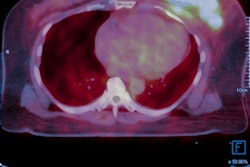

The research showed that ImaginAb's CD8 zirconium-89 (Zr-89) IAB22M2C agent was well tolerated with no immediate or delayed side effects, according to the firm. The biodistribution of the agent also suggested that CD8+ T cell-rich tissues were successfully targeted. The observed targeting of tumor lesions indicates the agent may be helpful for assessing the accumulation of CD8+ T cells within tumors, the company said.